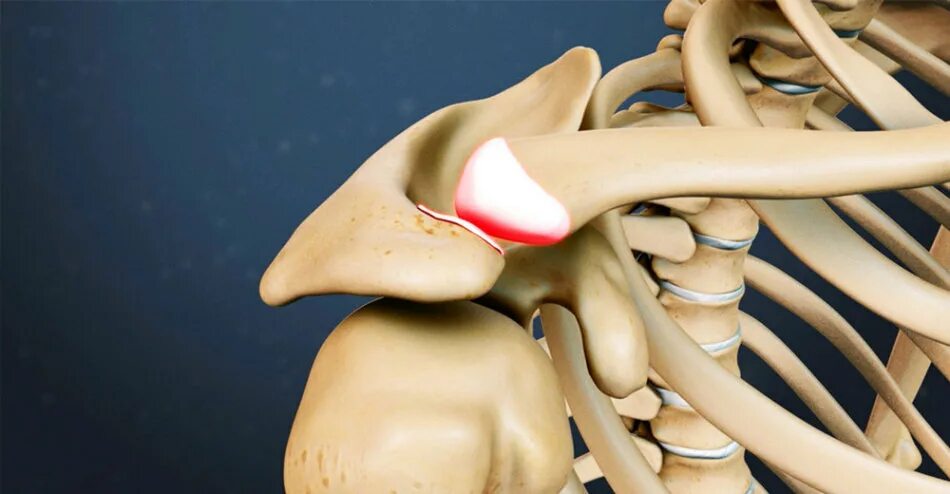

Артроз ключично акромиального сочленения плечевого